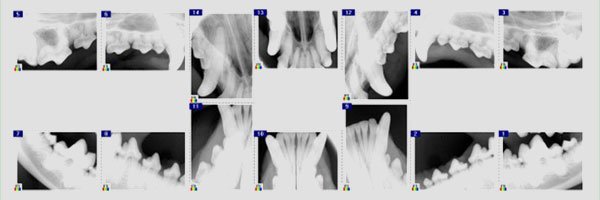

The Visiting Vet now offers and highly recommends digital dental X-rays (radiography) during all dental cleanings. Since approximately 70% of the teeth are not visible with just an oral examination, dental X-rays allow us to evaluate the teeth below the gum line to check for painful dental issues such as resorptive lesions, periodontal diseases, fractures, and much more. We purchased a digital dental X-ray system and began using it in December 2016.

Dr. Rotigel decided to practice her new dental X-ray system on her dog, Derby and her cat, CoCo in early January 2017. She knew that they were both due for their yearly dental cleaning but besides mild – moderate dental tartar, no other issues were noted on routine oral examination, even under anesthesia.

Derby’s dental X-rays looked good although there were 2 suspicious areas on her upper PM4 tooth roots which will be monitored and radiographs will be repeated in 6-12 months. For CoCo, unfortunately there were 3 big issues found with dental X-ray that would have been otherwise missed. He had 2 lower canine teeth with painful resorptive root lesions and there was a buried upper incisor root tip. All 3 of these teeth needed extraction. See the below discharge information sheet for CoCo.